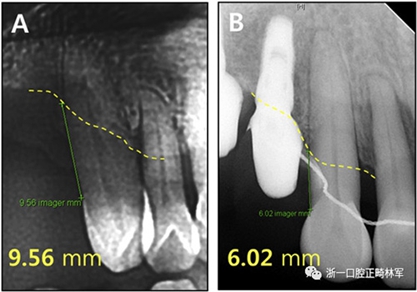

根據(jù)治療前后的根尖X光片,可以發(fā)現(xiàn)存在3.5mm顯著改善的放射線骨水平(圖15),并且臨床上牙周袋深度減少(表IV)。此外,力的推入性成分在向遠中移動期間誘導(dǎo)了上頜切牙的推入,并且在根尖X線照片上看到牙槽骨水平的改善。同時,如果種植體首先定位在磨牙區(qū)域,則可以通過使用種植體的臨時修復(fù)作為支抗來控制該力學(xué)過程。這種方法的優(yōu)點在于它解決了患者的主訴,即通過逆轉(zhuǎn)上頜前牙的張開和用最小程度的外科手術(shù)取代缺失的后牙進行咬合來重建咬合和美學(xué)。但是當(dāng)施加推入力時,在力作用線上施加一個垂直方向的力是不利的。完成整個治療需要花費很多時間,并且在正畸治療期間臨時修復(fù)體可能被破壞。

圖15.上頜右側(cè)尖牙放射性骨水平:A,治療前;B,治療后